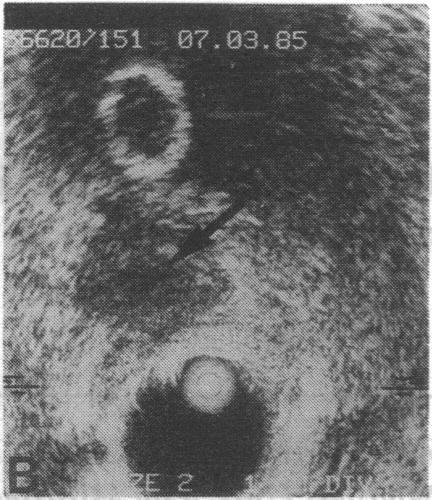

An unusual place to find hydatid.

J R Soc Med. 1987 Feb;80(2):118-9. doi: 10.1177/014107688708000219.

An unusual place to find hydatid.发现包虫的一个不寻常的地方。